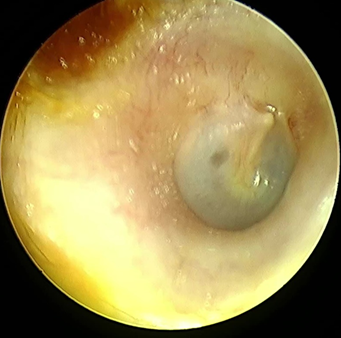

homolateral otalgia. In the examination, normal otoscopy (figure 1), there was no facial palsy, no spontaneous

nystagmus.

figure 1: otoscopy of the right ear